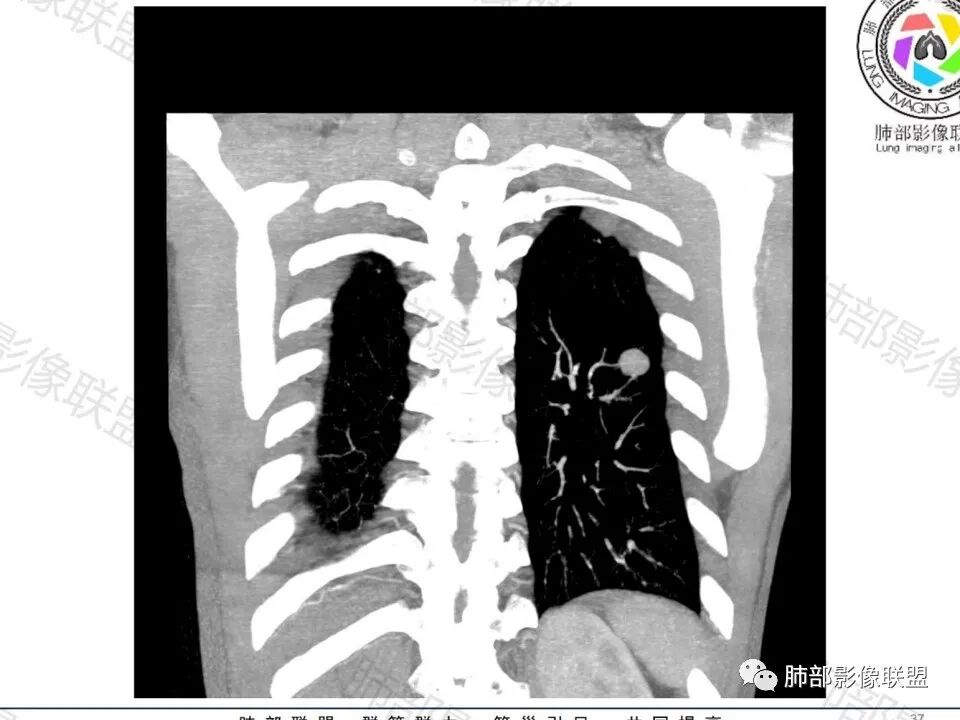

图做的真漂亮!老年男性,双肺多发结节,最大者位于左肺下叶胸膜下,周围有晕,晕中毛刺,边缘有一囊腔,胸膜牵拉,持续强化,考虑隐球,鉴别腺癌。

左肺下叶胸膜下类圆形结节,边缘光滑,周围有晕,晕中有毛刺,周围可见小卫星灶,相邻胸膜增厚,血管进入,右肺中叶可见小结节影,考虑炎性肉芽肿,隐球菌。鉴别腺癌。

老年男性,左肺下叶背段胸膜下结节,边缘毛刺,血管进入,斜裂有牵拉,局部胸膜糊墙,周围有晕,但有一囊腔,首先考虑腺癌,但是右肺中叶及左肺下叶还有其他结节,鉴别隐球菌

类圆形,边缘稍平直,周围晕中细微毛刺,密度均匀,均匀强化,血管走形自然,稍牵拉扭曲,支气管在近端堵塞

多发类似结节

1、炎性结节,多发,类似,晕,隐球菌?

2、恶性:多发:转移瘤?肺癌并多发转移瘤?